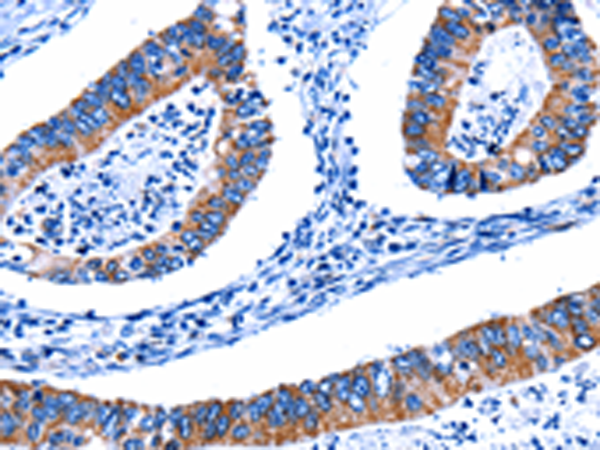

分类: 科研抗体货号: P00239别名: CTSU; CATL2; CTSL2应用: WB,IHC反应种属: Human, Mouse